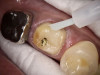

The benefits and ease of a universal bonding agent are demonstrated through the following case example of a Class II restoration. The patient was a 56-year-old woman. At her initial examination, it was observed that her lower right first molar (tooth No. 30) had an old failing amalgam restoration on the occlusal and a mesial fracture line with clinically visible caries (Figure 1). The preoperative bitewing x-ray did not show any mesial caries. The tooth needed a new restoration. The treatment plan was to perform a mesial-occlusal composite filling. A bitewing and periapical x-rays were taken to make sure that there was no other interproximal caries or any periapical lesion. Furthermore, an intraoral photograph taken with an intraoral camera was used to present and to help confirm the caries.